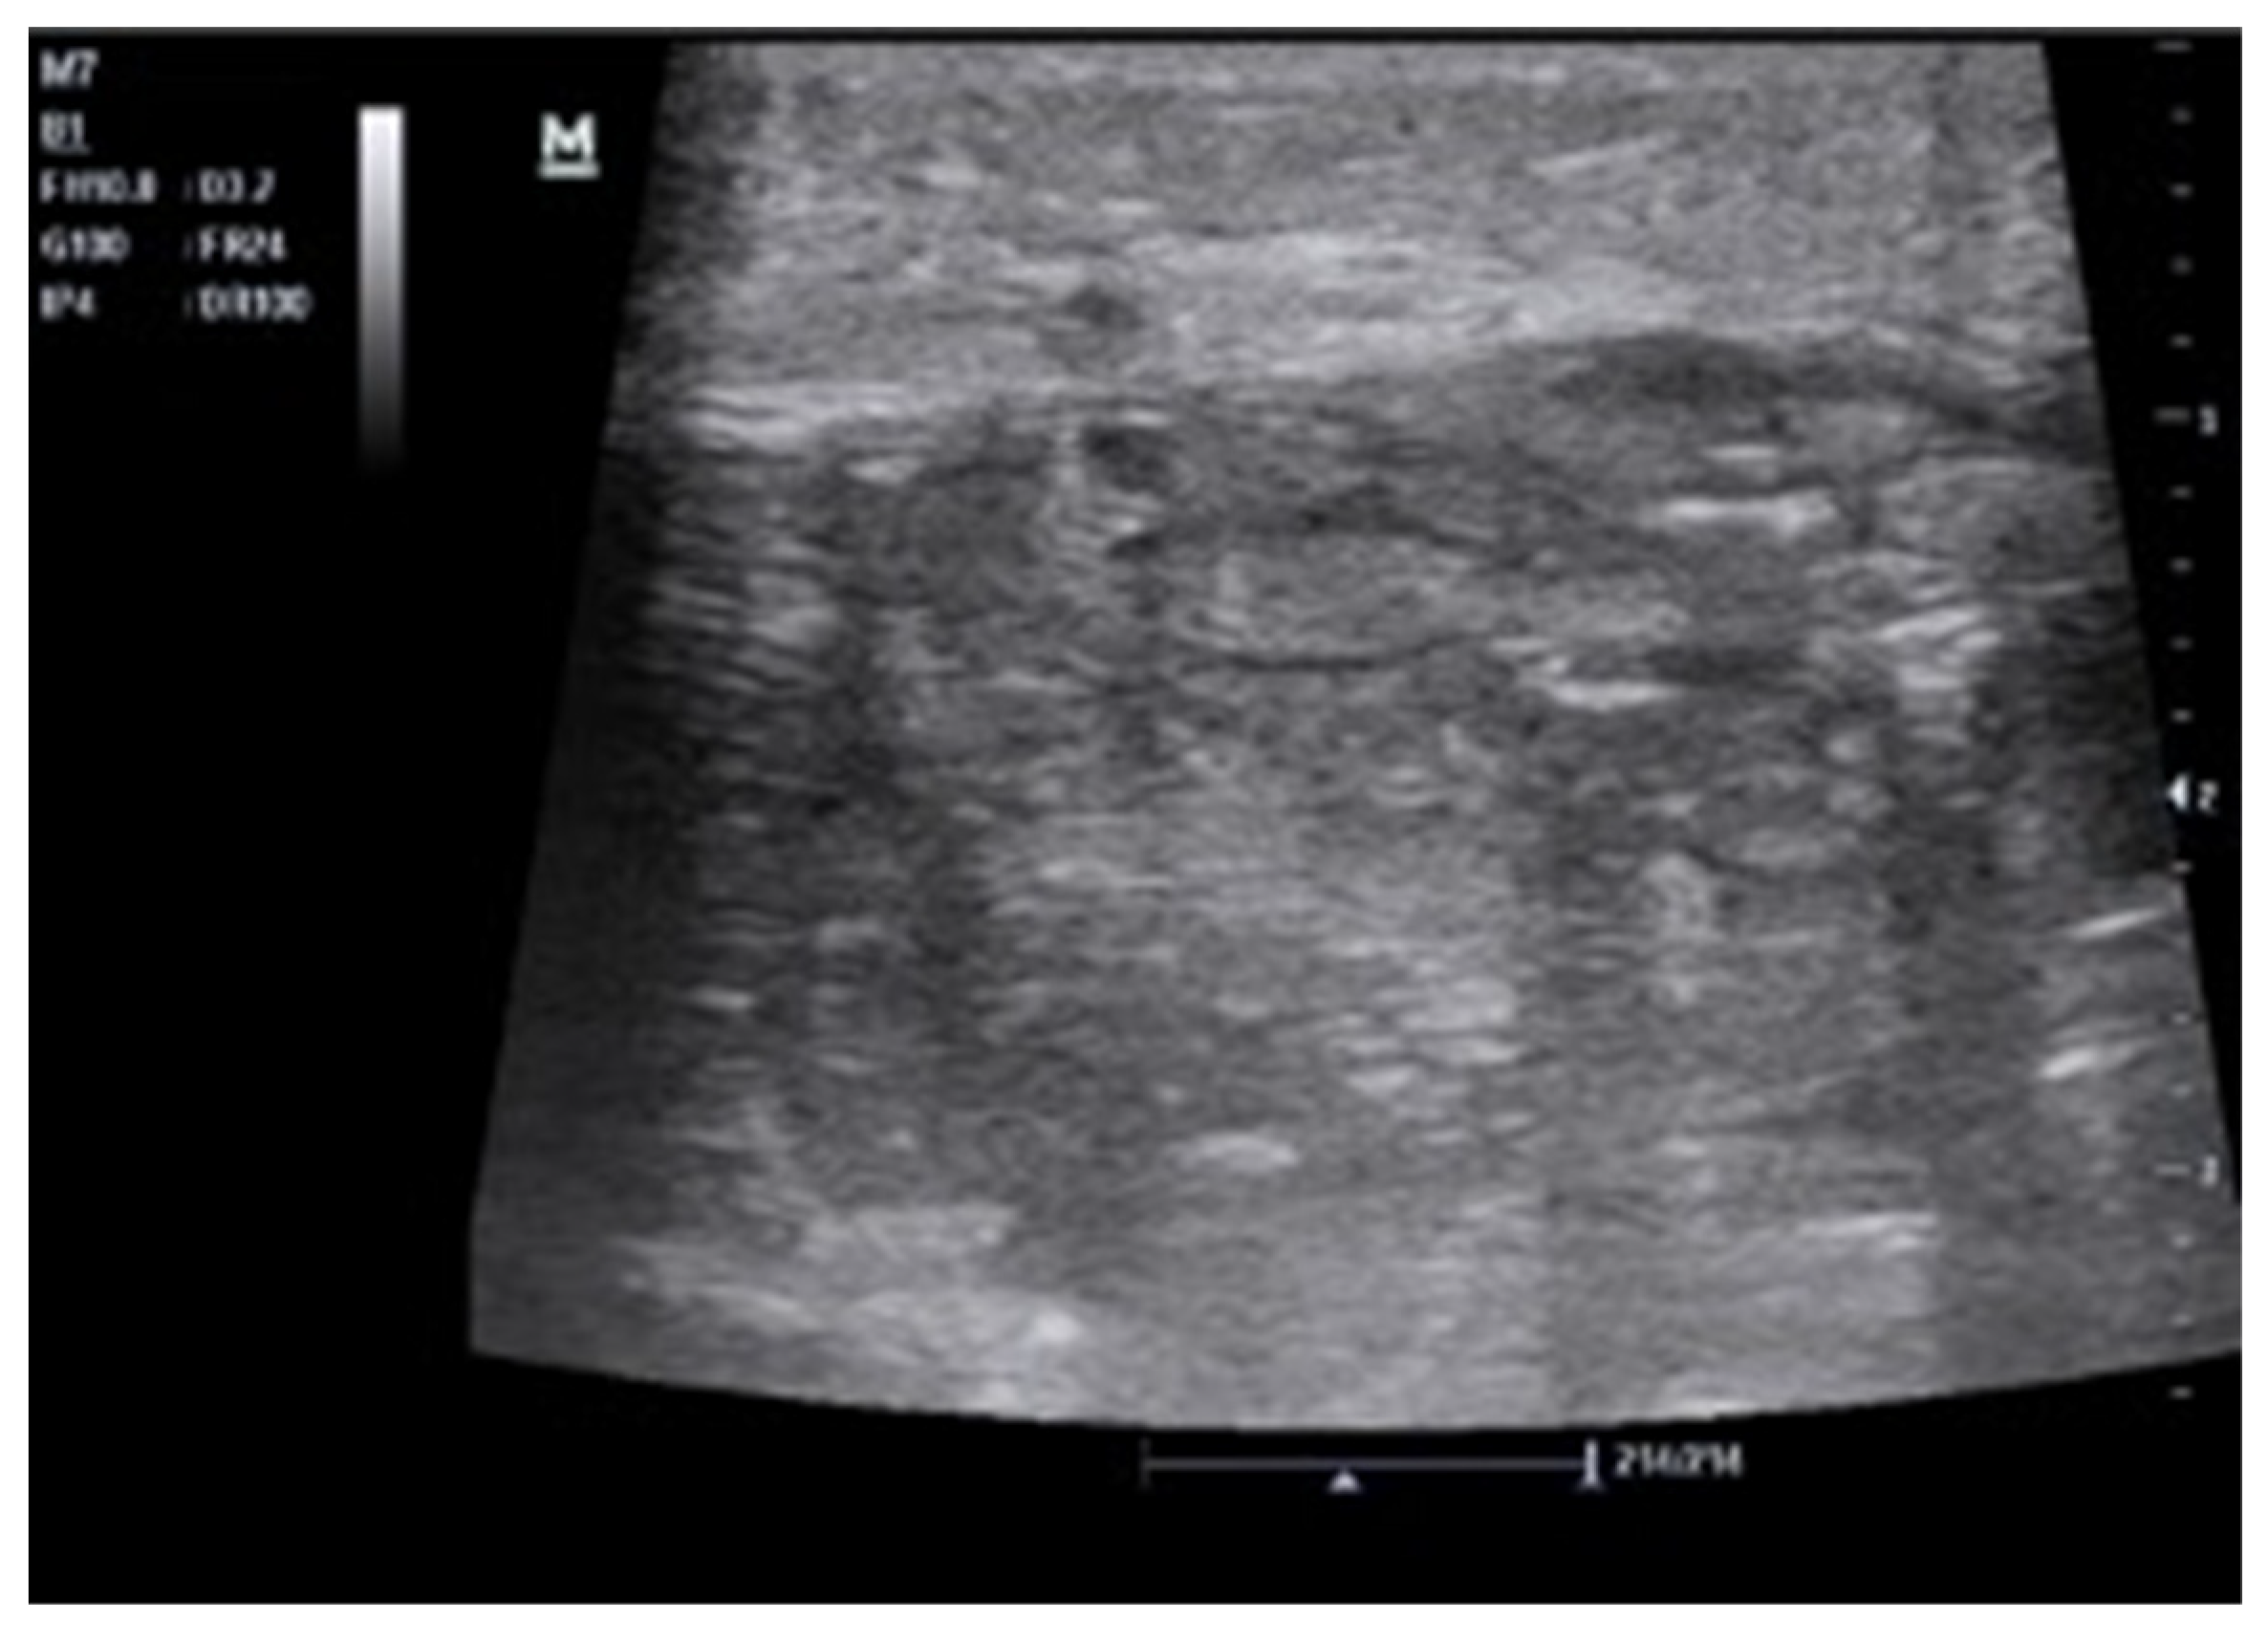

Intraparenchymal Fluid Lesions

| Intraparenchymal | Infected cyst Infectious cyst Hematoma Abscess Aneurysm Pseudoaneurysm |